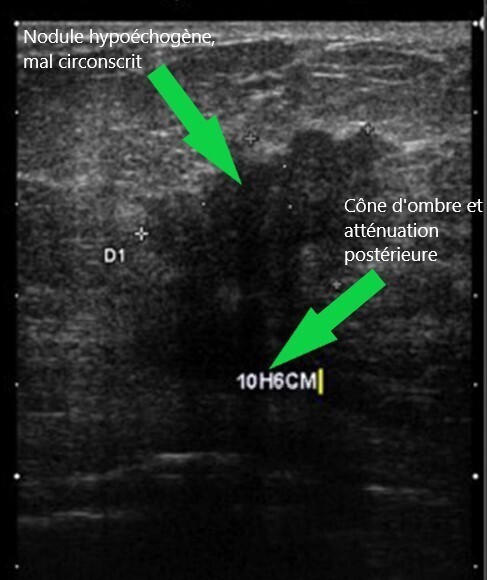

Mammographie du sein G : Échographie du sein G :

Question 10 - Concernant ces résultats, vous notez que (une ou plusieurs réponses exactes) :

Le nodule est hypoéchogène.

Les deux examens sont en faveur d’une lésion maligne.

La mammographie et l’échographie retrouvent un nodule spiculé de 41 mm du quadrant supéro-interne du sein gauche.